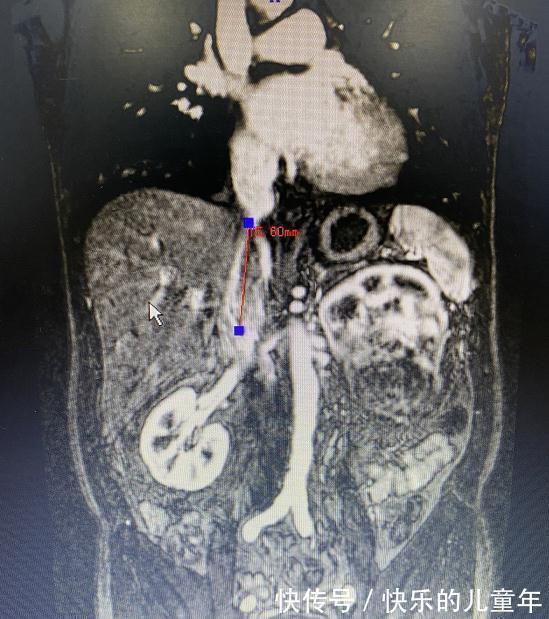

CT检查发现,除了左肾肿瘤并发左肺转移瘤,还伴有左肾静脉-下腔静脉癌栓,癌栓长度达7.5cm需手术治疗。

【影像检查可以看到癌栓长度大小。】